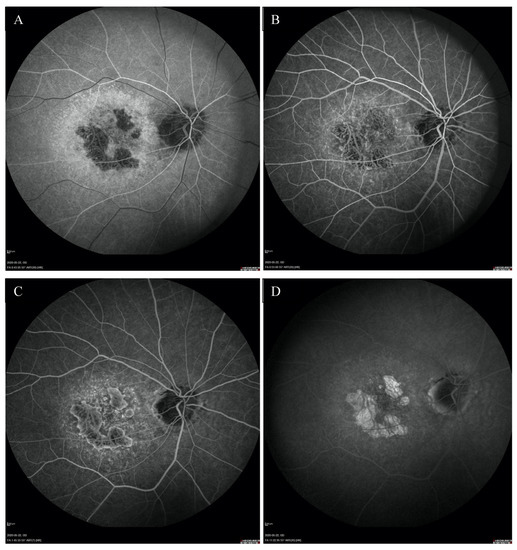

Fundus autofluorescence (FAF) showed a centrally located area with irregular borders showing hypoautofluorescence because of RPE atrophy with a surrounding rim of hyperautofluorescence consistent with RPE damage. There was an area of hypoautofluorescence around the optic discs at the site of atrophy as well. (Figure 1C,D). The above changes correlated with the visual field. Fundus fluorescein angiography (FFA) revealed granular hyperfluorescence in the macula and concomitant areas of fenestrated loss with visible choriocapillaris. The contrast flow through the main vessels did not show any obvious abnormalities (Figure 4A–D).

Figure 4.

FFA of the right eye (A–D) revealed the presence of granular hyperfluorescence in the macular and concomitant areas of capillary atrophy.